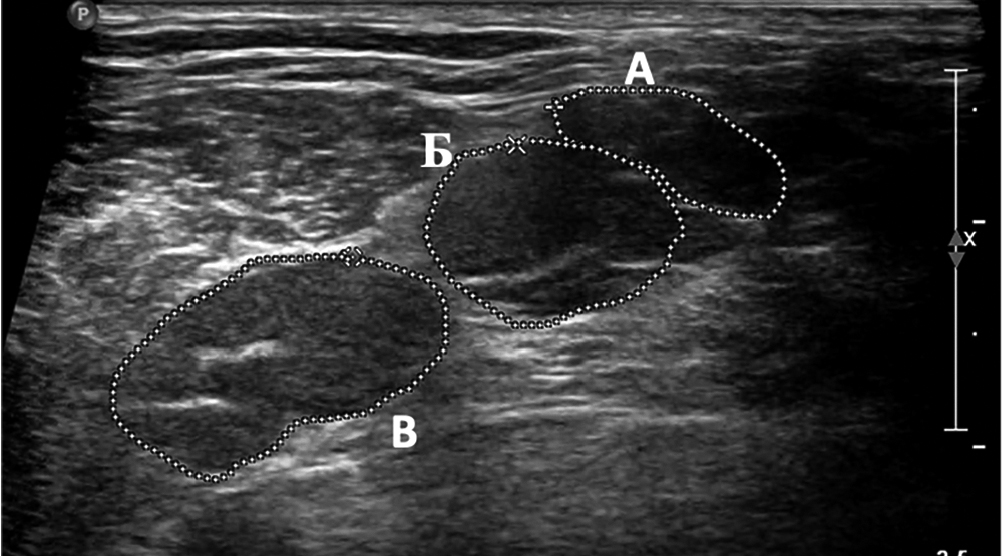

Увеличение диаметра спинномозговых нервов и ППС стволов ПС при УЗИ данных структур выявлено у 26 (87%) пациентов с ММН и у 32 (94%) пациентов с мХВДП. При этом исключительно односторонние изменения визуализировались у 6 (23%) из 26 пациентов с ММН и 3 (9%) из 32 пациентов с мХВДП (рис. 2).

Рис. 2. Сонографическое исследование стволов ПС у пациента с мХВДП (катамнез 8 лет, исследование выполнено до начала патогенетической терапии). При поперечном сканировании в межлестничном промежутке визуализируются три первичных ствола с увеличением ППС верхнего до 33,6 мм2 ( А), среднего до 68,9 мм2 ( В) и нижнего до 94,8 мм2 (С) (норма < 8 мм2).

Fig. 2. USG of BP trunks in a patient with MADSAM (8-year follow-up history, pre-therapy assessment). In the cross section, three primary trunks are seen in the scalene part, with enlarged upper (≤ 33.6 mm2; А), middle (≤ 68.9 mm2; В),

and lower (≤ 94.8 mm2; С) primary trunks (reference < 8 mm2).